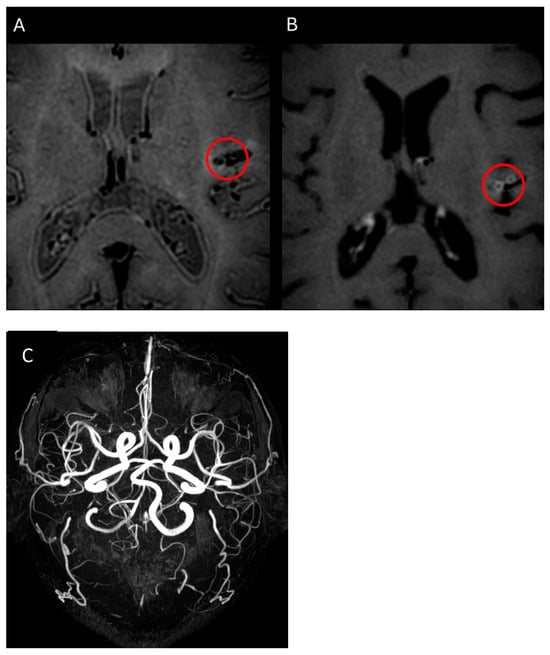

| Sugiyama S, 2023 [22] | F, 42 | 13 | N/A | Fever, mental confusion, spatial neglect | P/T | No | C/M | Multifocal arterial aneurysm and stenoses | CYC/antiplatelet | CR |